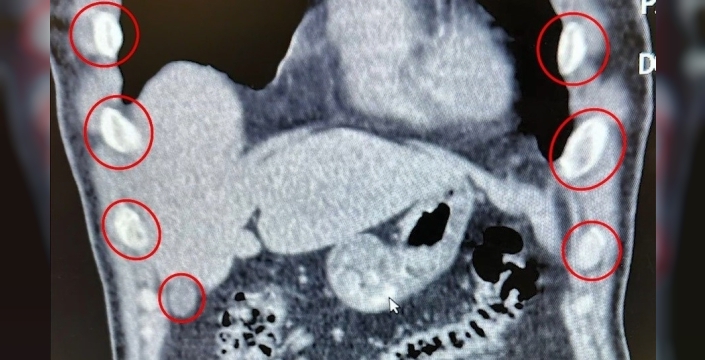

SERHED HABER - Bitlis İl Emniyet Müdürlüğü Narkotik Suçlarla Mücadele Şube Müdürlüğü ekipleri, uyuşturucu ile mücadele kapsamında önemli bir operasyona imza attı. Tatvan ilçesinde durdurulan bir otobüste yolcu olarak seyahat eden yabancı uyruklu 2 kişi gözaltına alındı. Şahısların yapılan tıbbi müdahalesinde, yuttukları 136 kapsül halinde toplam 1 kilo 48 gram metamfetamin ele geçirildi.